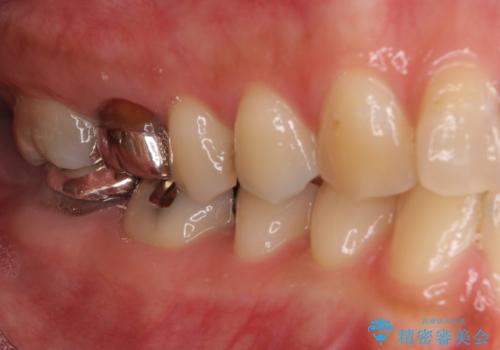

- 長年むし歯を放置してしまっているとのことで来院された患者様です。

神経が除去されている歯、根管治療の必要な歯、むし歯の非常に大きな歯に対してオールセラミッククラウンにて補綴治療を行うこととしました。